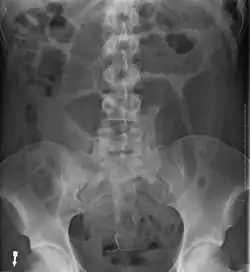

- Abdominal x-ray – tire-like shadow arising from the right iliac fossa and passing to the left

-

Coffee bean sign in a person with sigmoid volvulus -